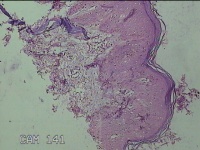

骶尾部皮肤结节

性别

男

年龄

39岁

临床诊断

皮下结节

一般病史

发现骶尾部皮肤结节2年余。

标本名称

大体所见

灰白粉红色组织2.3x1.7x0.3cm一块,表面带梭形皮肤2x1.3cm,皮下见结节1.8x1.2cm一个,切开结节呈囊性,囊内充满大量灰白色角化物,囊壁厚0.1cm。